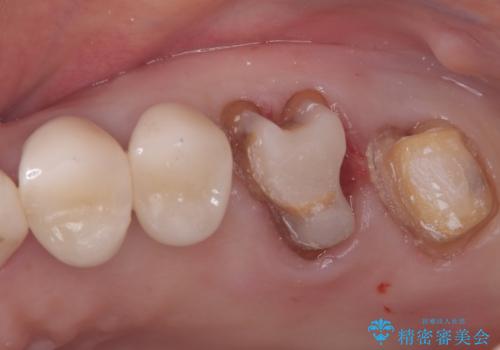

- 左上6番と7番の奥歯に、それぞれ遠心分岐部病変と頬側分岐部に10mmの深い歯周ポケットを認め、慢性的な炎症があります。再根管治療後も経過観察を続けましたが、病状の改善や歯周組織の付着が見られず、外科的歯内療法も選択肢にはありましたが、予後が不確実であること、そして患者様の負担を最小限に抑えたいというご意向を受け、抜歯即時埋入インプラントによる治療計画を立案しました。通常1年ほどかかる治療期間を大幅に短縮し、3ヶ月での機能回復を目指します。

今回のケースでは、特に難しいとされる奥歯の抜歯即時インプラントを適用しました。まず、炎症を起こしていた左上6番と7番を慎重に抜歯し、その直後にインプラントを埋入。この抜歯即時埋入により、歯を失ってからインプラントを埋入するまでの期間を省くことができ、骨の吸収を最小限に抑えられました。痛みや腫れもほとんどなく、患者様は「思ったより楽だった」と仰っていました。結果的に、通常であれば1年近く要する治療をわずか3ヶ月で完了。機能性と審美性を兼ね備えた新しい奥歯により、快適な食生活と笑顔を取り戻していただけました。